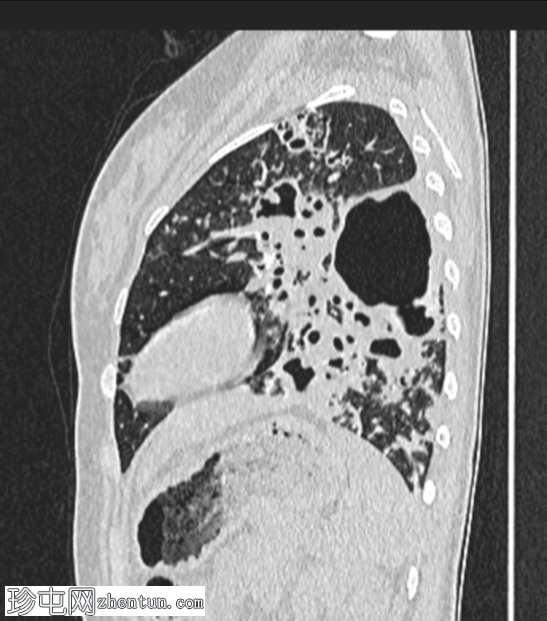

双侧肺部可见气腔实变和空洞,肺壁厚(左上叶和左下叶最大),伴支气管周围增厚,多发树芽征和结节征。

Gene Xpert MTB-RIF 检测,痰液结核杆菌阳性

痰涂片抗酸杆菌(3 份),Z.N 染色阳性